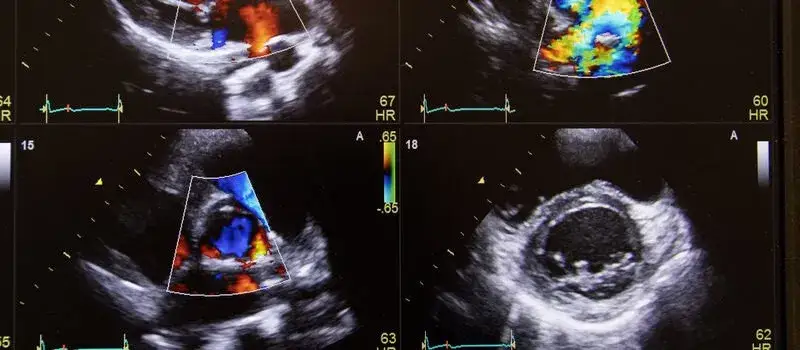

Ultrasonografia nerek, znana jako USG nerek, to nieinwazyjna metoda diagnostyczna, która pozwala na ocenę struktury i funkcji nerek. Podczas badania lekarz wykorzystuje fale dźwiękowe, aby uzyskać obrazy nerek oraz otaczających je tkanek. USG jest szczególnie przydatne w wykrywaniu zmian anatomicznych, takich jak torbiele, guzy czy kamienie nerkowe.

Badanie to jest szybkie i bezpieczne, a także nie wymaga specjalnego przygotowania ze strony pacjenta. USG nerek może pomóc w diagnozowaniu problemów, takich jak niewydolność nerek, choroby zapalne czy urazy. Dzięki tej metodzie lekarze mogą uzyskać istotne informacje na temat przepływu krwi przez nerki oraz ich wielkości i kształtu, co jest kluczowe dla dalszej diagnostyki.